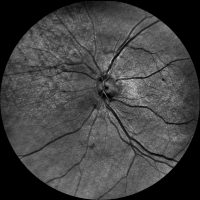

Dzięki technologi SLO – Scanning Laser Ophthalmoscope, podczerwieni oraz wiązki zielonego laseru, jesteśmy wstanie wykonać bardzo dokładny zrzut dna oka, dzięki czemu wykryjemy praktycznie każde zmiany w gałce ocznej. W realizacji takiego skanu nie potrzebne jest zakroplenie oka co znacznie usprawnia nam diagnostykę pod katem szybkości badania czy samopoczucia osoby poddanej tejże czynności. Badanie ma na celu wykrycie zmian w oku jak: jaskra, zaćma, zatory żylne, męty, retinopatie cukrzycową czy AMD(zwyrodnienie plamki żółtej), Pełna wizyta obejmuje: